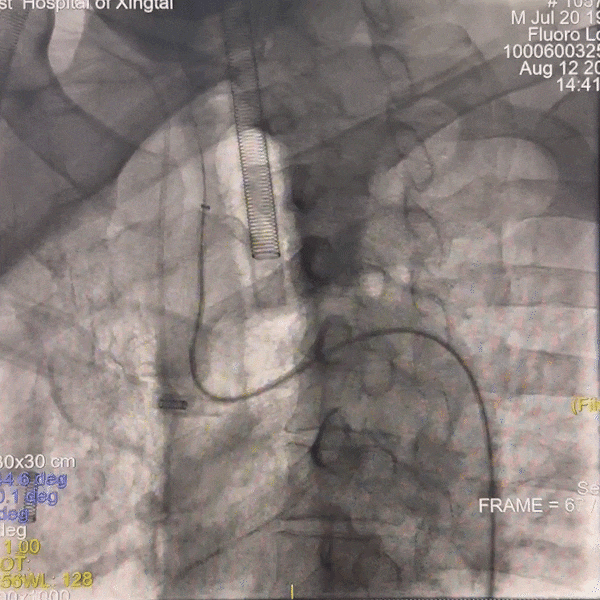

手术过程

通路建立:经桡造影显示Ⅲ型弓,病变为右侧颈内动脉C4段动脉瘤,患者桡动脉纤细不适合经桡治疗,故选择经股动脉应用赛诺神畅APEX TRA GC™5F-130 SIM2导引导管超选右颈,同轴长鞘建立通路。

动脉长鞘怎么置入一技之“长”丨经桡及经股困难入路应用赛诺神畅APEX TRA GC™导引导管建立通路病例合集_https://www.jmylbn.com_新闻资讯_第20张

Ⅲ型弓

动脉长鞘怎么置入一技之“长”丨经桡及经股困难入路应用赛诺神畅APEX TRA GC™导引导管建立通路病例合集_https://www.jmylbn.com_新闻资讯_第21张

SIM2导管成袢

动脉长鞘怎么置入一技之“长”丨经桡及经股困难入路应用赛诺神畅APEX TRA GC™导引导管建立通路病例合集_https://www.jmylbn.com_新闻资讯_第22张

超选入无名动脉

跟进长鞘至右侧颈内动脉。

动脉长鞘怎么置入一技之“长”丨经桡及经股困难入路应用赛诺神畅APEX TRA GC™导引导管建立通路病例合集_https://www.jmylbn.com_新闻资讯_第23张

栓塞动脉瘤;致密栓塞AN后复查造影。